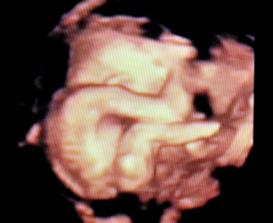

✿♥♥♥♥Bude to dievčatko!!!!! ♥♥♥♥✿

Bude to Stella 🙂

krasne 3D sono 🙂